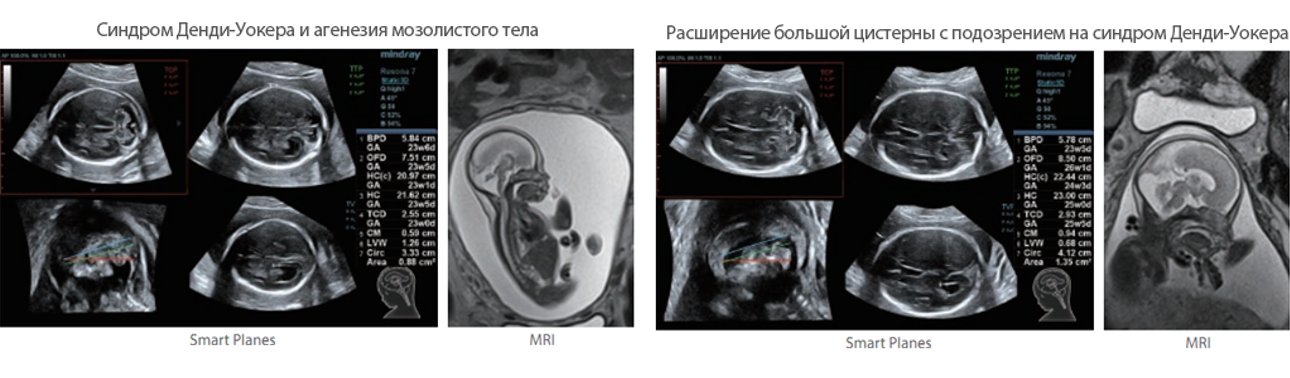

Обеспечивая качество изображения уровня премиум, Resona 7 также повышает клинические возможности исследования при помощи революционной системы V Flow, предназначенной для оценки гемодинамических показателей сосудов; обеспечивает интеллектуальное получение из 3D данных наиболее важных проекций для диагностики ЦНС плода. Сочетая в себе интуитивно понятное сенсорное управление с распознаванием жестов и все важные клинические характеристики, передовая система Resona 7 настоящая новая волна в сфере ультразвуковых инноваций.Благодаря перечисленным выше характеристикам, Resona 7 является доступным решением премиум-класса, которое удовлетворяет высоким требованиям клинической точности и эффективной диагностики в условиях современной перегруженной больничной среды.